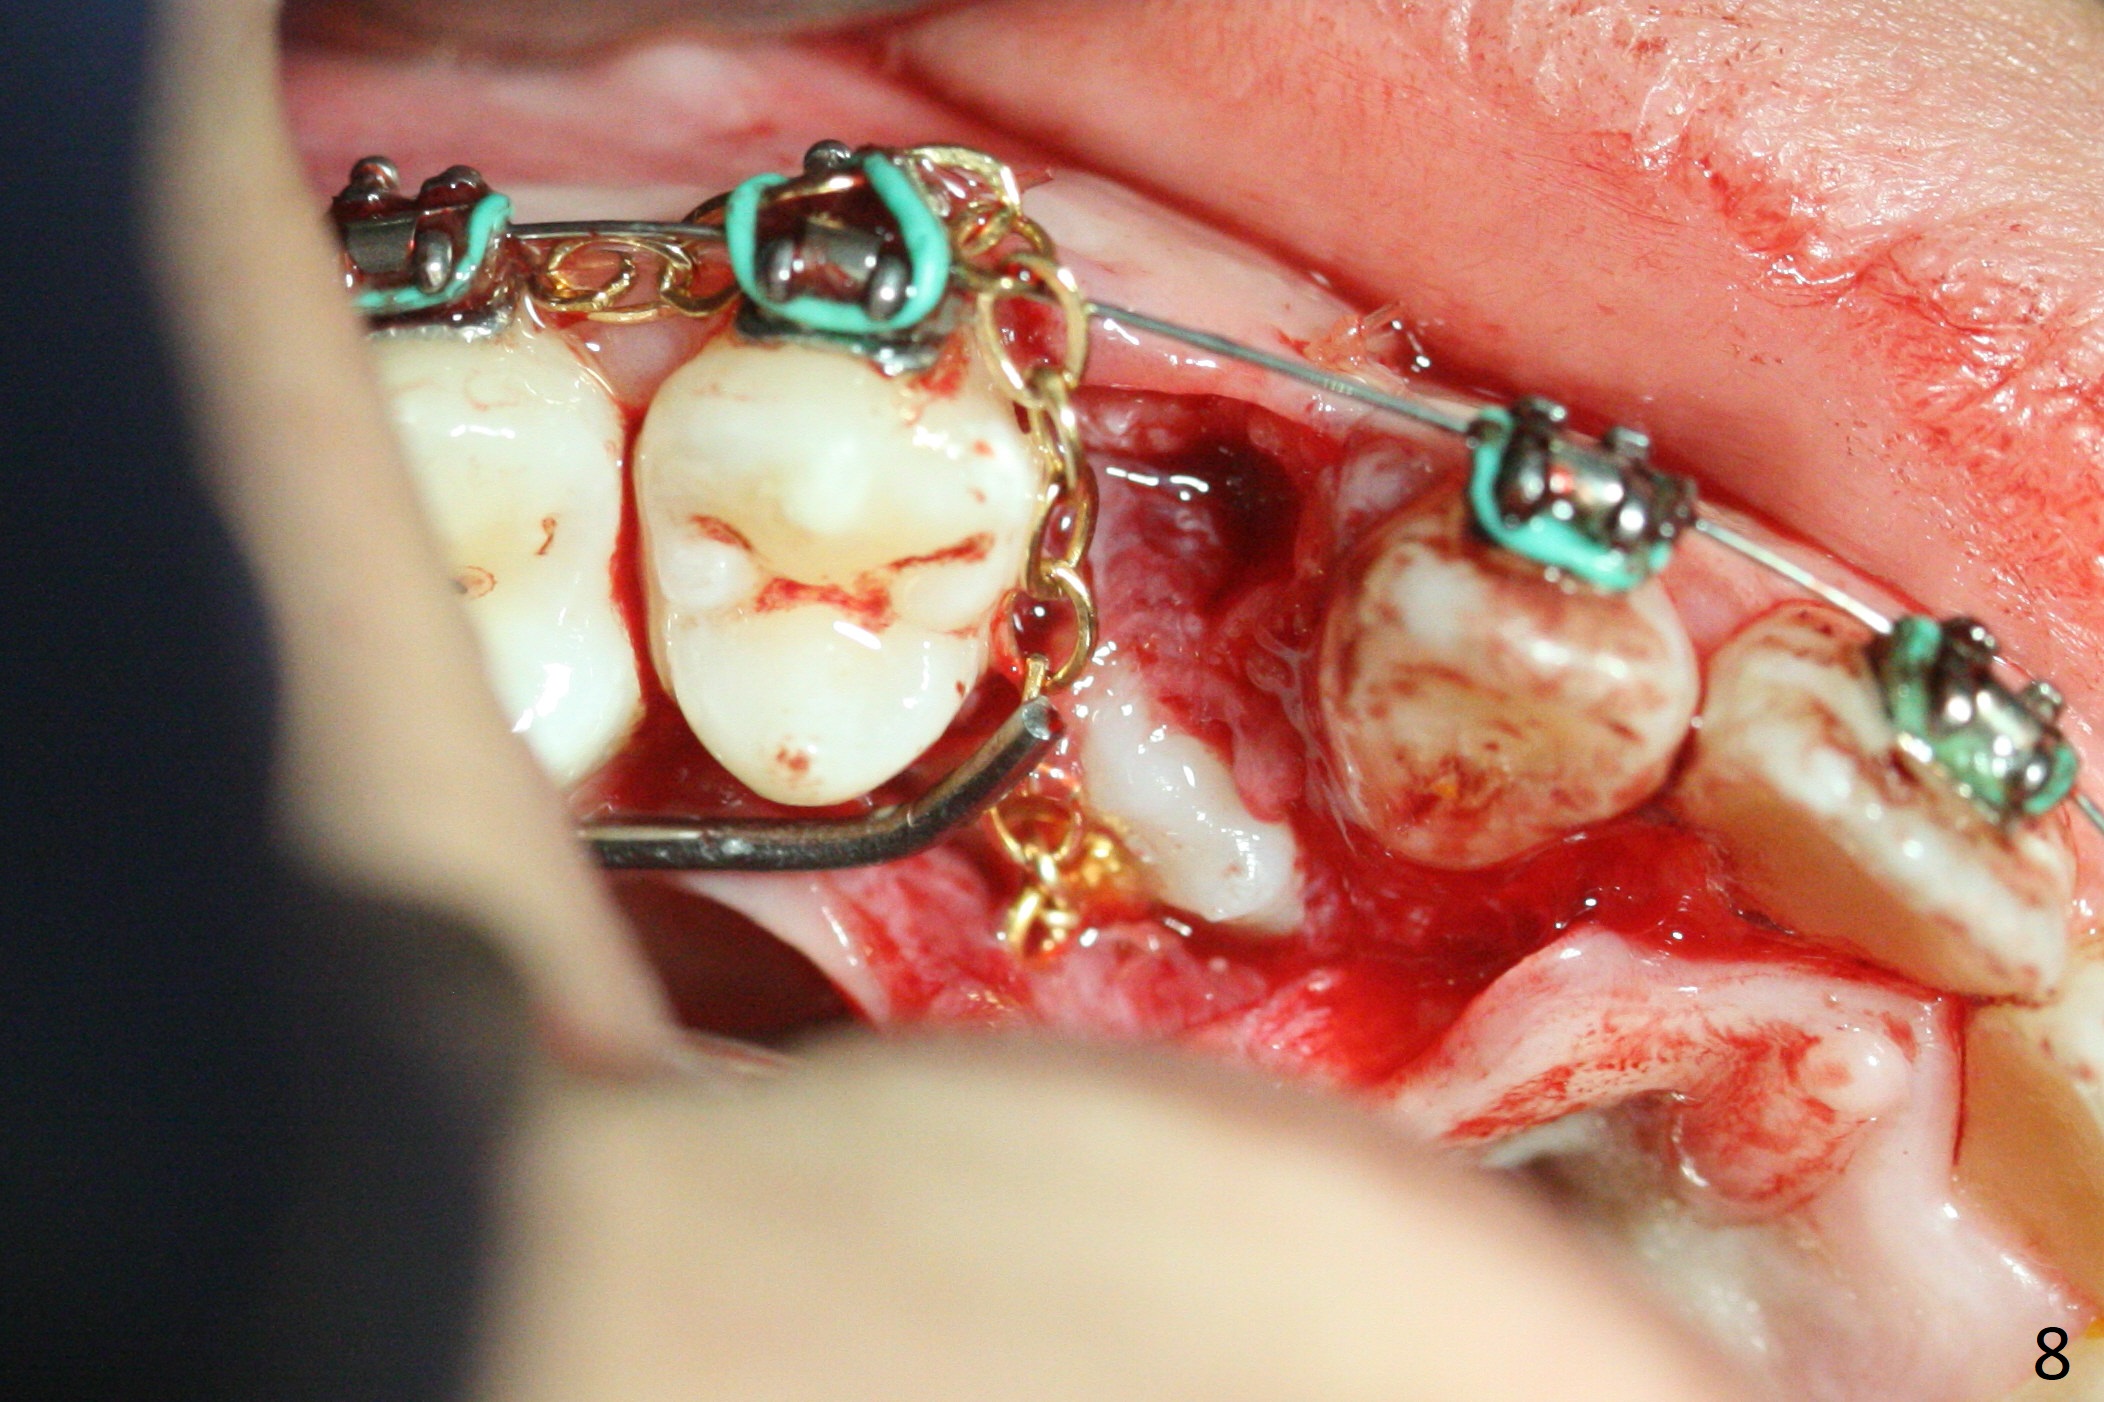

A 13-year-old woman has an impacted canine (Fig.1 (6)) and retained deciduous one (C). After initiation of orthodontics, she returns for surgical access to the impacted canine and placement of device to facilitate eruption (Fig.2,3). Incision is made buccal (Fig.4), but there is no tooth buccal (Fig.5). Extraction of the deciduous canine does not reveal the impacted one (Fig.6), but there is palatal elevation (*). Palatal access shows the impacted tooth (Fig.7) and allows placement of a retraction device (Fig.8). Careful clinical exam and CBCT are necessary diagnostic steps.